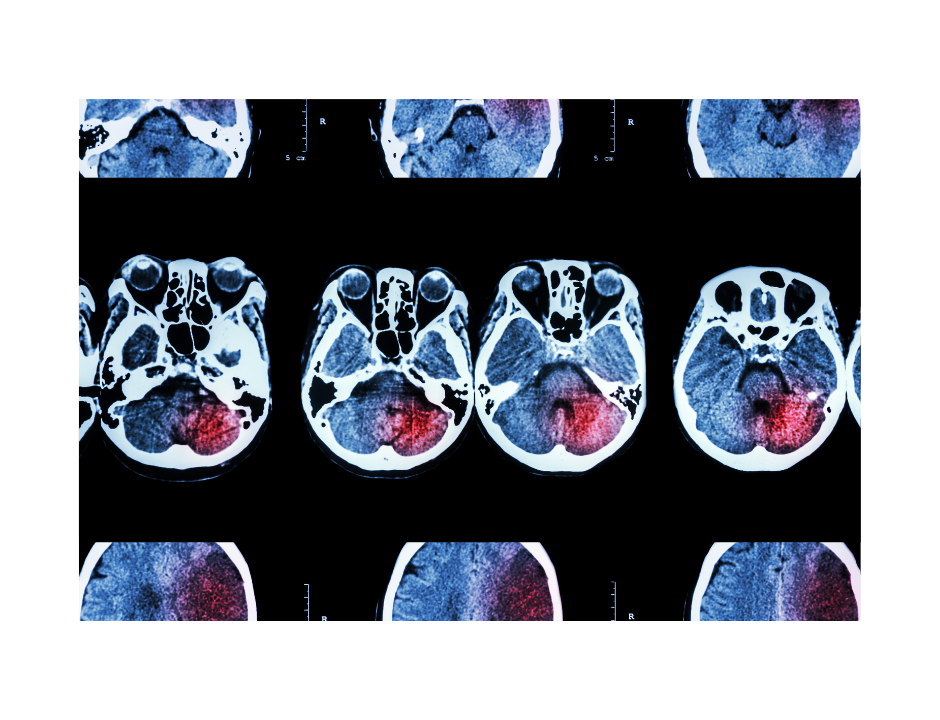

May is Stroke Awareness Month Did you know that Stroke is the leading cause of adult disability in the US, 2nd leading cause of death in […]